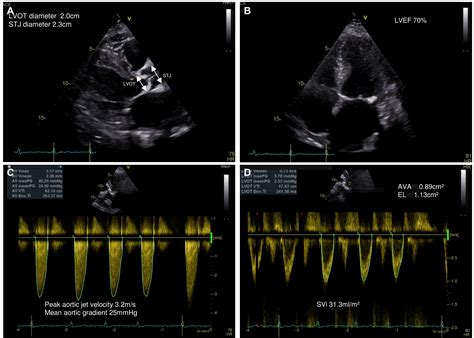

Physicians typically diagnose Severe Aortic Stenosis through a combination of physical examinations and advanced imaging technologies. The most common diagnostic tool is the echocardiogram, which provides a real-time visualization of the valve’s movement and measures the severity of the obstruction.

Transthoracic Echocardiogram (TTE) Valve area, pressure gradient, and left ventricular function.

• severe aortic stenosis gradient